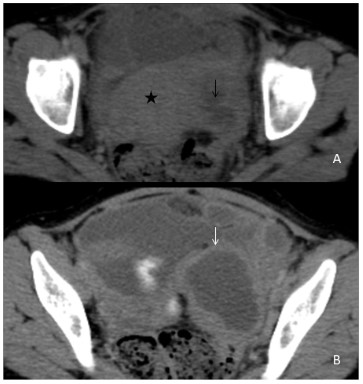

Genitourinary tuberculosis

Genitourinary tuberculosis is the second most common site of tuberculosis, caused by Mycobacterium tuberculosis, secondly to pulmonary tuberculosis. It can be divided anatomically into renal tuberculosis (renal parenchyma, calyces and renal pelvis), bladder and ureteric tuberculosis, prostatic tuberculosis, scrotal tuberculosis, tuberculous pelvic inflammatory disease (female). The kidneys are the most common site of GUTB. Clinical presentations are hematuria, frequency, urgency, dysuria with involvement of the bladder. Stricture formation is the most common complications in GUTB. Common sites of stricture formations are the neck of a calyx causing hydrocalyx, regional hydro calcinosis, pelvic-ureteric junction causing generalized dilatation of pelvicalyceal system and lower end of the ureter. Other imaging findings are parenchymal scars & irregularity of the papillary tips (motheaten calices), and small cavities in the papillae. (Figure 10A,10B,10C,10D) Sometimes fibrotic reactions may develop, leading to stenosis and strictures formations. Chronic tubercular infections in the genitourinary tract result in a ‘thimble bladder’ appearance and patulous VUJ (Figure 10E,10F). In females, pelvic tuberculosis is seen commonly in India, leading to a tubo-ovarian abscess or stricture formation (Figure 11A,11B).

Figure 12: (A,B) A 35 years old female presented with pain abdomen and irregular menstrual history. Contrast-enhanced computed tomography images at the level of the pelvis in the axial plane demonstrate a peripherally enhancing elongated tubular structure with incomplete internal septations (black arrow) in the left adnexal region ( white arrow) adjacent to the uterus (black star), suggestive of inflammatory tubo-ovarian. A mild amount of free fluid is seen in the abdominal cavity. Diagnostic ascitic tapping revealed increased ADA level (68IU/L) with increased lymphocyte counts suggestive of tubercular aetiology. ATT was immediately started, and the patient is on follow up to look for the size of the abscess. If the lesion size does not decrease, a surgery will be done.

Conclusion